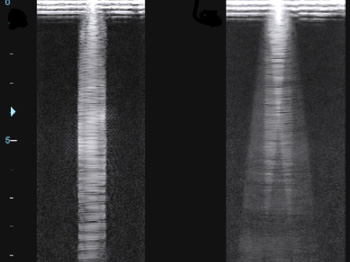

Панорамное сканирование. Панорамное сканирование поможет вам просмотреть даже неподвижные анатомические структуры. При этом полностью реконструируется поверхность исследования, которая состоит из отдельных кадров. Чтобы получить целостную картину, вам нуж

Анатомический М-режим. Благодаря этой функции вы получите возможность сделать до трех срезов одновременно в реальном времени, вращая курсор под произвольным углом без перемещения датчика. Таким образом, врач может увидеть графику движения структур сердца

Ультразвуковая томография. Другое название данной функции, мультислайдинг, таит в себе ответ на вопрос о ее назначении. Данные, полученные вами во время первоначального трехмерного сканирования, пополняются за счет просмотра нескольких двухмерных срезов.